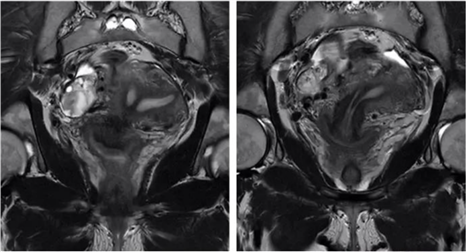

双子宫

双侧副中肾管未融合,各自发育成两个子宫、宫颈和阴道。75%伴阴道纵隔或斜隔

两个独立的子宫、宫颈、阴道,T2WI解剖分层正常

双角子宫

双侧副中肾管在子宫顶端未融合

两个分开的宫腔,宫底凹陷,两侧宫角距离增大,腔内分隔组织信号特征与子宫肌层一致